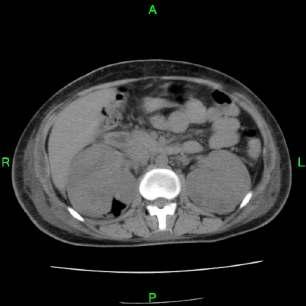

Emphysematouspyelonephritis–inanon-diabeticyoungwomen

—arareassociation— Y S Ravikumar, K M Srinath, L S Adarsh, Manjunath S Shetty, Subrahmanyam Karuturi, B Balaji Kirushnan .................................................108 Rhinocerebralmucormycosis:reportoftwocasesandreviewofliterature — Gopee E Makwana, Vikash Jain, Nandini Bahri, Mala Sinha, Manish Kumar Mathur.................110 Harlequinichthyosis—acasereport— Sendhil Coumary A, Seethesh Ghose .................................113 ..............................................................................................................................................116